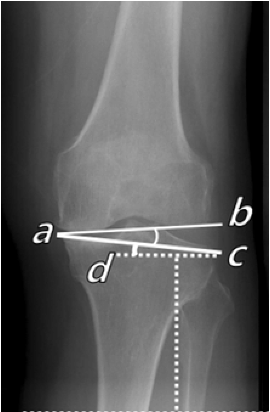

Preoperative deformity analysis in the frontal plane according to Paley [13]

Determination of weight bearing line (Mikulicz line), MPTA (medial proximal tibia angle), mLDFA (mechanical lateral distal femoral angle) and the mechanical varus angle are the 4 key parameters of analysis in the frontal plane (Fig. 1a). The joint line obliquity (JLO) and joint line congruence angle (JLCA) are used as extended parameters for the planning of a double level osteotomy (DLO) in varus deformities on the femur and the tibia as well as the bony correction angle in any varus thrust (Fig. 1b).

With a medial open-wedge correction of the tibia, the MPTA angle should be no more than 94° after the correction, because otherwise the joint line obliquity (JLO) is more than plus 4°, which results in clinically relevant shear forces in the joint and to poorer clinical outcomes.

Cases of major correction (>10°) are almost always due to a combined deformity of femur and tibia. If the deformity is mainly on the femur, the correction must be performed at the femur. In around 10−15% of cases no acceptable joint line obliquity (JLO) can be achieved with only one correction on femur or tibia. In these cases a simultaneous double level osteotomy (DLO) correction on the femur (lateral closing wedge) and tibia (medial open wedge) should be performed [16−17].

Planning with calculation of the correction angle was performed according to Miniaci [18] (Fig. 1e). Planning can be performed either manually or using digital software. It is important when planning the bone correction angle that an abnormal joint line convergence angle (JLCA) (see Fig. 1b) is included in the planning (alpha angle minus JLCA >2°) because otherwise the osteotomy will result in an overcorrection to valgus deformity.